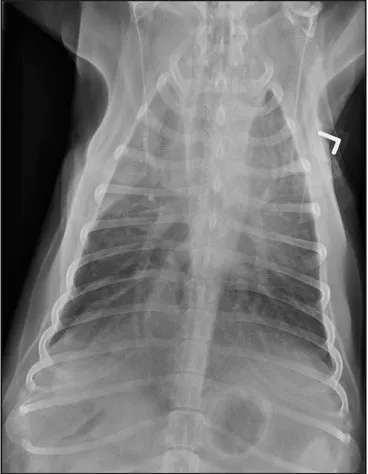

CASE 1.1 A 7-year-old neutered male Labrador Retriever who was hit by a car. You obtain these thoracic radiographs: Figs. 1.1a, b, left and right lateral projections, respectively; Figs. 1.1c, d, ventrodorsal and dorsoventral projections, respectively.

1.1c